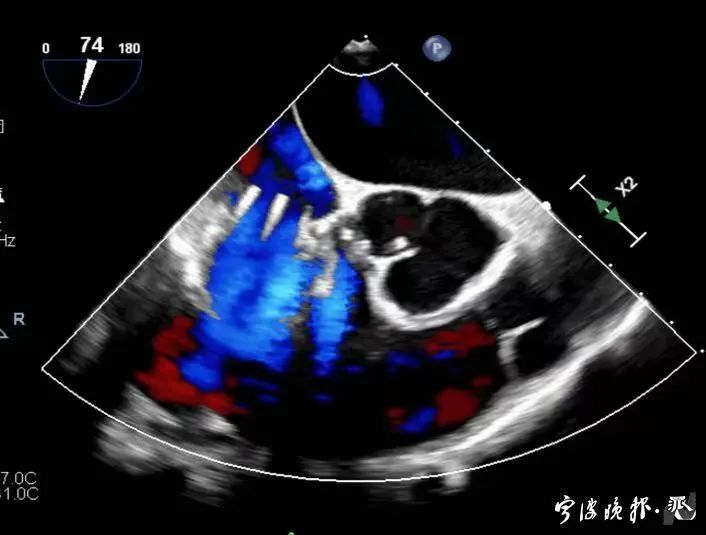

術(shù)后食道心超示三尖瓣反流消失

得知可以微創(chuàng)手術(shù),陳大爺一家決定放手一搏。寧波市醫(yī)療中心李惠利醫(yī)院心臟瓣膜中心團(tuán)隊(duì)反復(fù)就術(shù)前準(zhǔn)備、手術(shù)步驟及術(shù)后可能出現(xiàn)的各種情況做了預(yù)案。3月4日,陳大爺?shù)氖中g(shù)成功進(jìn)行,術(shù)中得到LuX-Valve經(jīng)導(dǎo)管三尖瓣置換術(shù)原創(chuàng)團(tuán)隊(duì),上海長海醫(yī)院陸方林主任團(tuán)隊(duì)的鼎力支持,術(shù)后陳大爺?shù)男呐K三尖瓣反流立即消失。術(shù)后瓣膜中心CCU(心臟監(jiān)護(hù))團(tuán)隊(duì)和心內(nèi)科團(tuán)隊(duì)迎接一個(gè)又一個(gè)右心瓣膜置換后的血流動力學(xué)改變等帶來的挑戰(zhàn),克服種種難關(guān),二周后患者進(jìn)入早期心臟康復(fù)。目前陳大爺已經(jīng)順利出院,沒有胸悶氣急,生活自理,精神狀態(tài)也很好,瓣膜中心團(tuán)隊(duì)也在對他持續(xù)隨訪中。